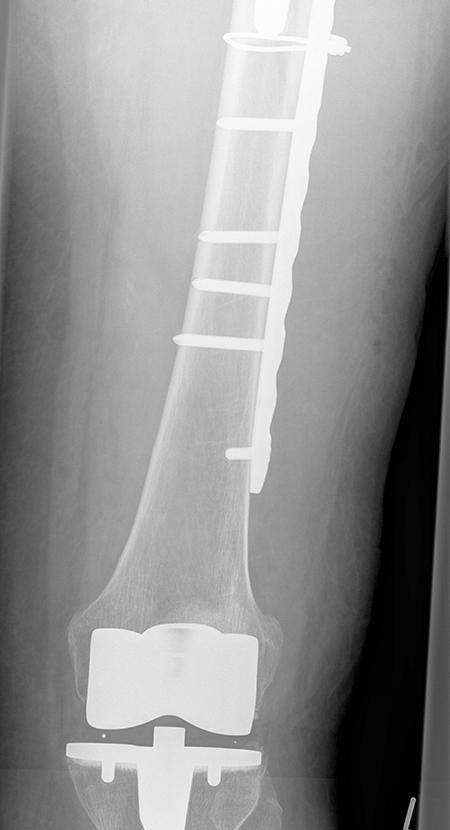

Periprothetische Fraktur - Hüftschaft stabil (Vancouver B1) - liegende Knie-TEP

Knochenbruchbehandlung mit Spezialplatte und Drahtcerclagen um den stabilen Hüftschaft herum

Lange Platte zur Neutralisation der Kräfte